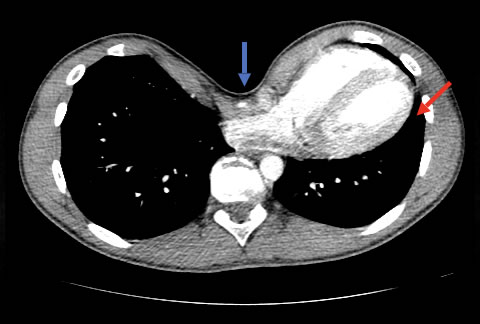

Chest CT showing significant sternal depression (blue arrow) of the heart and left lung (red arrow)

Compression of structures in the chest secondary to the deformity can cause a decrease in internal chest volume and can lead to heart and lung impingement. It is suggested that symptoms may worsen with age, but the significance of the functional or physical effects of pectus excavatum is controversial and remains an important topic of debate.

The effect of sternal displacement pushing backwards particularly in severe pectus excavatum is obvious physically, on X-ray and on the echocardiogram (heart ultrasound scan). Patients often complain of a ‘constrictive’ feeling and palpations. In severe cases, it causes cardiac compression, and especially affects the right heart. However, like lung function, data from studies remains contradictory and with no consensus on whether the heart is significantly affected despite patient symptoms.